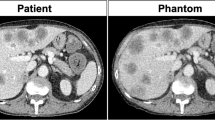

To evaluate the effectiveness of DLR in radiotherapy, the differences between the AIDR and CT values and image variability must be examined. Figure 1 shows the differences in CT values between AIDR and AiCE at various doses; AiCE was compared at three reconstruction intensities (Mild, Standard, and Strong). The variation in CT values of all reconstruction algorithms was large at low doses, that is, 25 mAs, and the difference in average CT values was insignificant, with less than 10 HU at doses of 100 mAs and above. Regarding the change in CT values with dose, no difference was observed in AiCE reconstruction intensity. Figure 2 shows the difference in CT values between AIDR and AiCE for each material. As shown in Fig. 1, the difference was small for 265 mAs and large for 25 mAs. When a sufficient dose was ensured, the variation in CT values from the AIDR was within 10 HU, and the uncertainty of the CT values was negligible (Fig. 2a). At low doses, there were changes of 20–30 HU in high-density materials and 0–20 HU near a CT value of 0 (Fig. 2b). Regarding the differences in AiCE reconstruction intensity, Mild showed CT values closer to the AIDR than Standard/Strong for high/low-density materials, and Standard/Strong was closer to the AIDR than Mild for CT values approaching zero. The influence of the difference in reconstruction intensity was negligible as the changes were all less than 5 HU.

The variation in CT values for each material is shown in Fig. 3. SD represents the standard deviation of the CT value, with each material as the region of interest. Interestingly, from Fig. 3, it can be observed that the SD of AiCE (Strong) is the lowest for all materials and doses. AiCE (Mild) showed almost no change in SD compared with AIDR at 265 mAs. However, at 25 mAs, where the lower dose was used, AiCE had a lower SD at all reconstruction intensities than AIDR (Fig. 3b). Figure 4 shows the CT value-to-electron density conversion (CT-ED) table. Low-dose AIDR showed a slightly changed CT value (Fig. 4b), while AiCE showed no change in CT value owing to changes in reconstruction intensity and dose.

This study aimed to assess the usefulness of DLR (AiCE) in treatment planning using large-bore CT. The current study found that AiCE showed less change in CT values and smaller SDs than AIDR. These results suggest that AiCE can be used in radiation therapy as well as AIDR, which has been widely used, and it can be expected to play a role in recommending uncertainty in dose calculations because of the low noise in the images. The noise reduction effect was particularly large in the low-dose region (Fig. 3b), indicating that AiCE may contribute to dose reduction in CT for treatment planning. Previous studies have shown that DLR algorithms reduce noise4,5,6,7,8,9, and the results of this study follow similarly.

It is well known that there are variations in organ delineation, and high-quality images can reduce delineation uncertainty in treatment planning22,23,24,25. This is a phantom-based study, despite demonstrating little change in CT values; furthermore, combined with the benefit of improved image quality, DLR may be useful for delineation. The AiCE Mild reconstruction showed little improvement in SD, suggesting that the reconstruction intensity should be stronger than that of Mild for treatment planning CT. The reconstruction kernel of AiCE in this study only considered the Body_sharp filter, and a multifaceted study is required. Images with low variability are also important for particle therapy. In particle therapy, CT images are used for range estimation26,27. DLR has been shown to reduce SD, and this method can be applied to particle therapy by evaluating the accuracy of calculating the stopping power.

Dose reduction in treatment-planning CT is another important topic28,29,30. Remarkably, in this study, AiCE showed stable performance, even at low doses. The difference between AiCE and AIDR became larger for low-density materials (Fig. 2b), but this was caused by the fluctuation of the CT values of AIDR (Figs. 2 and 4b). The CT values of AiCE showed very little change with dose (Fig. 4), and at low doses, an SD reduction was observed at all reconstruction intensities (Fig. 3). The difference in SD between Mild and Standard/Strong was large, again suggesting the usefulness of reconstruction intensities that were higher than Standard.